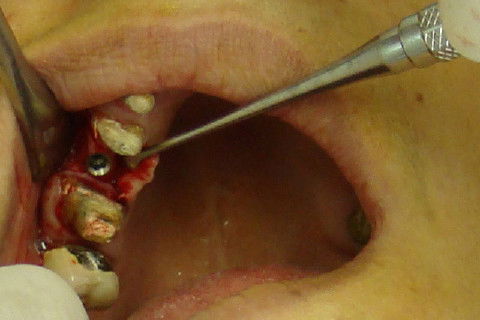

Abertura do retalho e inicio da remoção dos parafusos de osteossíntese na região 12

Abertura do retalho e inicio da remoção dos parafusos de osteossíntese na região 22